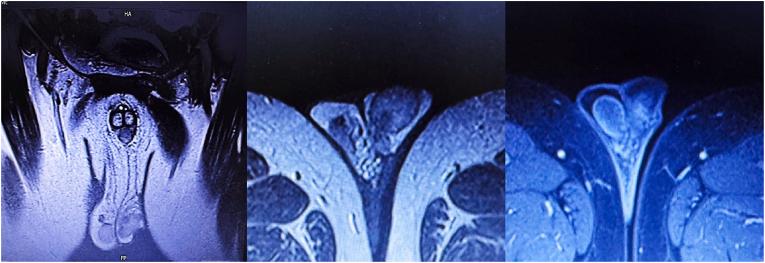

This case report presents a 61-year-old male patient diagnosed with high-risk prostate cancer who underwent hormone therapy and radiotherapy. Three years after beginning treatment, rising prostate-specific antigen (PSA) levels led to a PET CT scan, which identified isolated metastases in the left testicle. The patient then underwent a radical orchiectomy. One-year follow up revealed undetectable PSA and no evidence of any metastases. The significance of this case lies in the uncommon occurrence of testicular metastasis from prostate cancer, particularly when presenting in isolation after a prolonged period following hormone therapy and radiotherapy.

本病例报告介绍了一名61岁的男性患者,他被诊断为高危前列腺癌,接受了激素治疗和放射治疗。治疗开始三年后,前列腺特异性抗原(PSA)水平升高,于是进行了PET CT扫描,结果发现左侧睾丸有孤立性转移灶。该患者随后接受了根治性睾丸切除术。一年的随访显示PSA检测不到,且无任何转移迹象。本病例的意义在于前列腺癌发生睾丸转移的情况不常见,尤其是在激素治疗和放射治疗后的较长时间后单独出现。